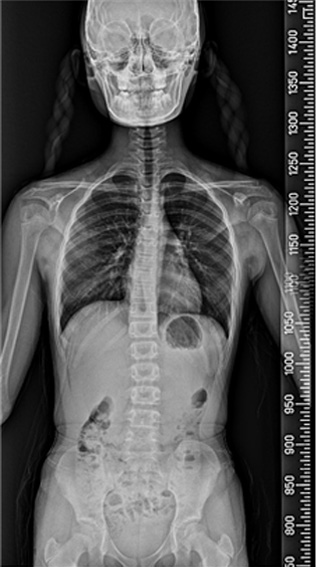

척추 측만증과 성장

척추 측만증은 80%가 사춘기 때 발생하며, 사춘기 여아의 10~14%, 사춘기 남아의 5%에서 나타나는 것으로 알려져 있습니다. 성조숙증이 있는 아이들은 더 어린 나이에 급성장이 온 것이기 때문에 척추 측만증이 생길 가능성이 더 높습니다. 성장호르몬 치료를 하는 경우에도 사춘기때처럼 급성장을 하기 때문에 척추 측만증이 생길 가능성이 더 높습니다. 물론 이는 약물 부장용이 아닌, 일종의 성장 부작용인 셈입니다. 척추 측만증은 심할수록, 골연령이 어릴수록, 그리고 역연령이 어릴수록 점점 더 심해질 가능성이 높으며, 따라서 가능하면 조기에 발견하여 치료하는 것이 좋습니다. (from Lonstein & Carlson) 이렇게 척추 측만증은 일종의 성장기 합병증으로 볼 수 있으며, 따라서 성장판이 닫칠 때까지 더 진행될 확률이 높고 대신 성장판이 닫치면 진행도 멈추게 됩니다.

척추 측만증 : 앉아 있기가 힘이 들며 어깨 높이가 다른등 척추 부위 통증 및 걸음걸이, 자세등에 다양한 불편감 호소.